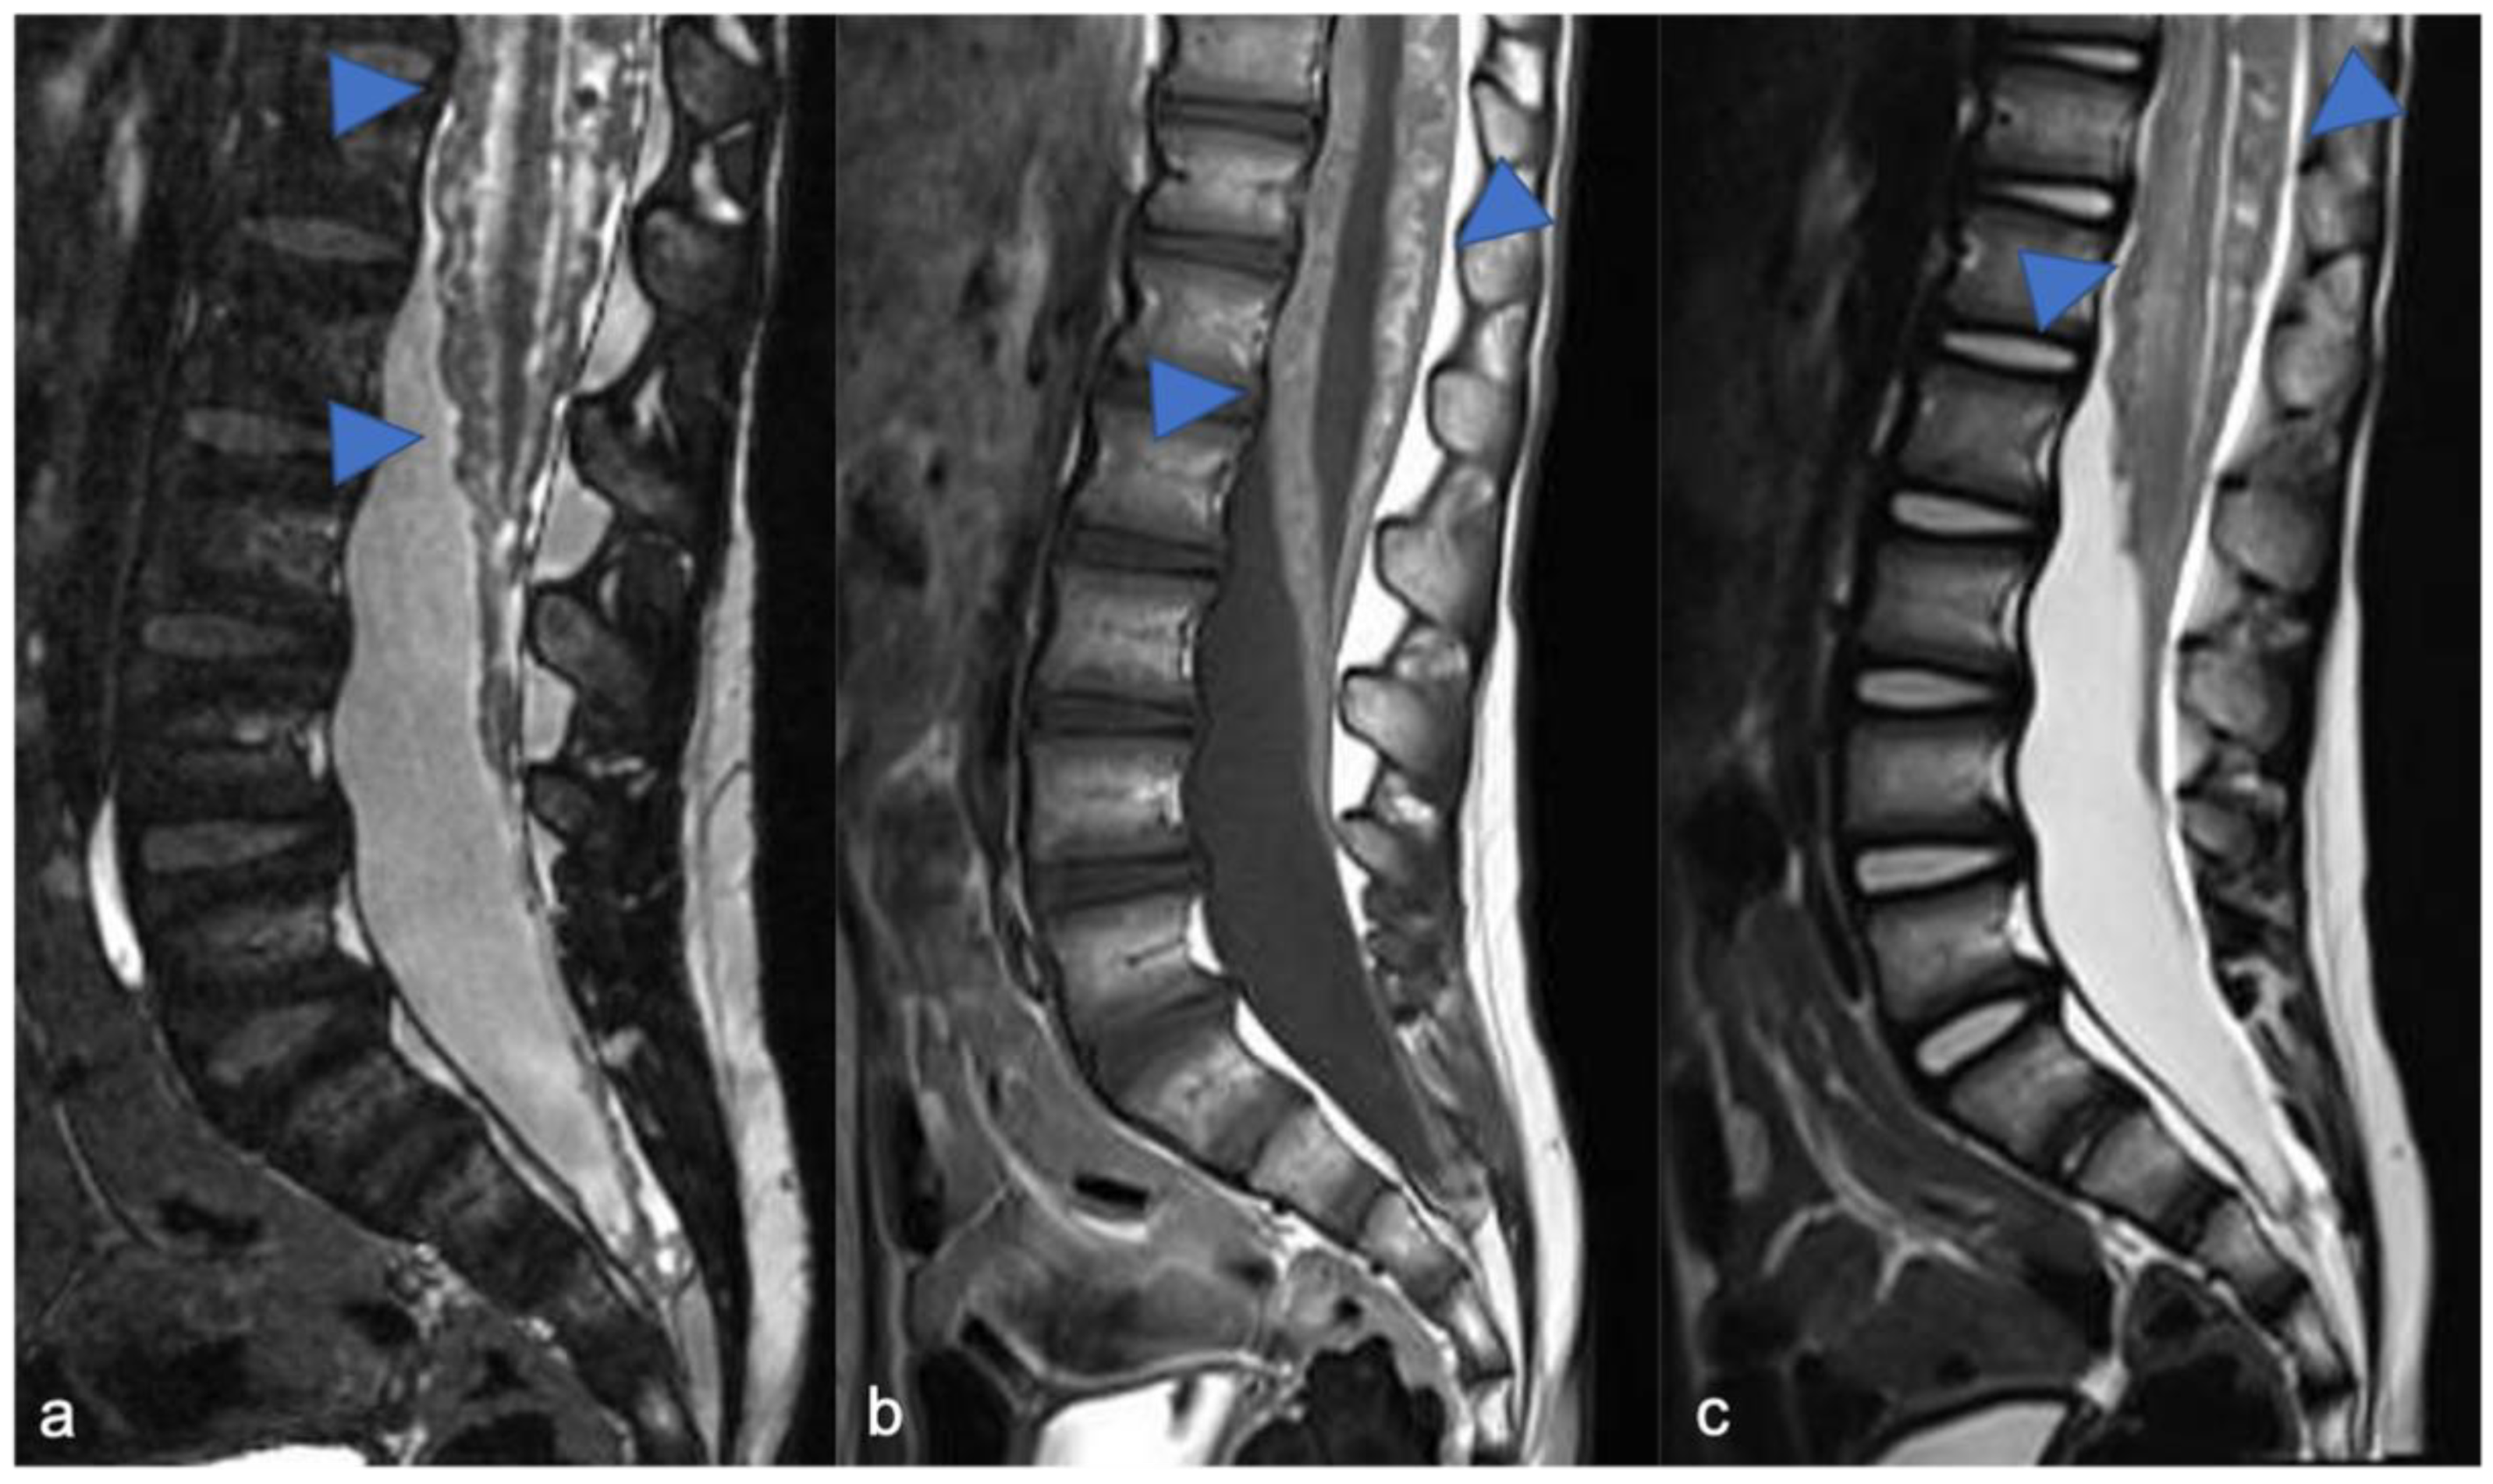

2. Gliomas and Mixed Neuronal–Glial Tumors

2.1. Gliomas